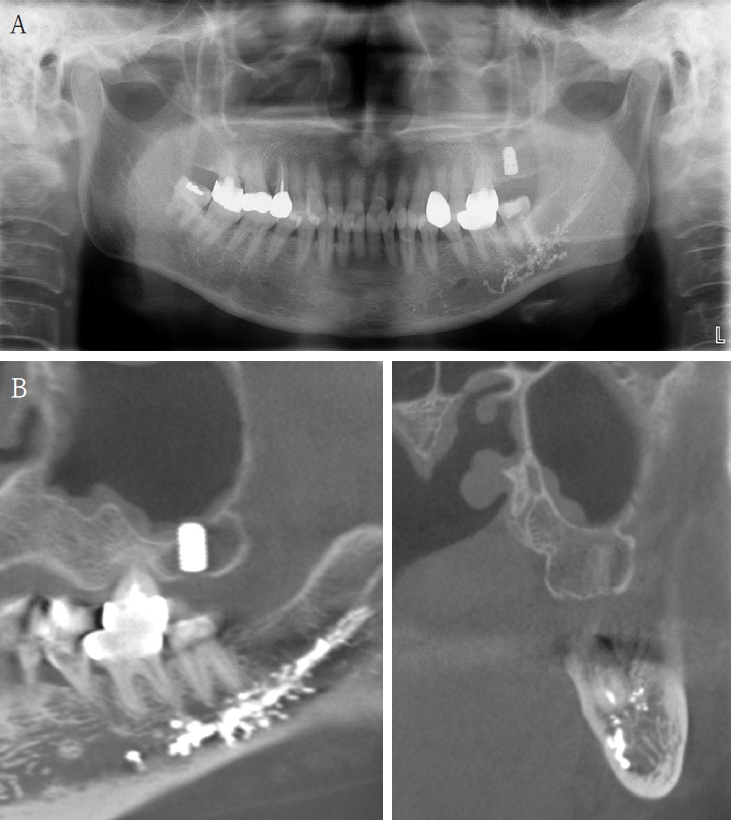

An 18-year-old male developed numbness in the right lower lip, gingiva, and chin following endodontic treatment of the mandibular right first molar (#46) at a military hospital 2 weeks ago. A panoramic radiograph and multi-detector computed tomography (MDCT) revealed extruded Calcipex II in proximity to the IAN (Fig. 6). Neurologic testing confirmed severe hypoesthesia in the right mentum region. Thermal discrimination was absent across a broad area of the right lower lip and chin. The patient’s subjective discomfort was rated as VAS 2. The patient underwent foreign body removal, nerve transposition, and bone grafting under general anesthesia (Fig. 7). At one-week postoperative follow-up, neurosensory testing showed little to no improvement. At the five-month follow-up, repeated neurosensory testing demonstrated meaningful improvement in directional discrimination and pin-pressure nociceptive discrimination, despite the continued presence of hypoesthesia. At the 17-month follow-up, testing revealed further improvement, including recovery of static light touch sensation, with overall symptoms classified as mild hypoesthesia. However, the patient reported worsening subjective discomfort, with a VAS 5, reflecting a discordance between objective sensory recovery and subjective symptom persistence.

Figure 6.

A. Pre-op panoramic radiograph of Case 4 patient. B. Pre-op MDCT of Case 4 patient